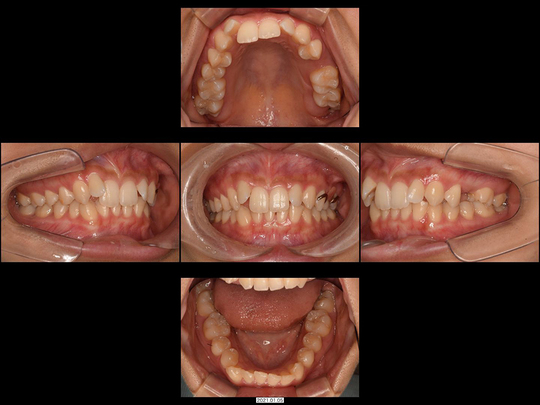

矯正前

画像をクリックで拡大

矯正後

治療の説明

左上2番目の前歯は生まれつきない(先天性欠如)と診断されていましたが、八重歯の隙間から歯が生えてきたため、改善したいとのご要望です。

審美的な面を優先して埋伏歯の左上2本を抜歯するのではなく、上下4番の抜歯とワイヤーによる全体矯正を併用。同時にCTを用いて、左上2番の埋伏犬歯を開窓牽引にて対応しました。また、術前のCT検査にて右上2番だけ片方が矮小歯(わいしょうし)であることが判明。左右2本の歯の大きさに著しい差が出るため、最終的に右上2番だけセラミックで修復することを想定して歯列移動をいたしました。セラミック修復前に両隣りの歯との間隔を矯正治療でより適切にスペース確保しておくことで、最終的に神経をとらずセラミック治療も行えました。

治療の期間・回数

24か月、30回

​費用

1,188,000円(セラミック治療を含む)